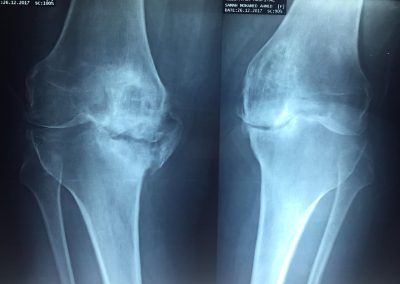

تم تركيب مفصل ذو مواصفات خاصه لتعويض عجز العظام بالركبة.